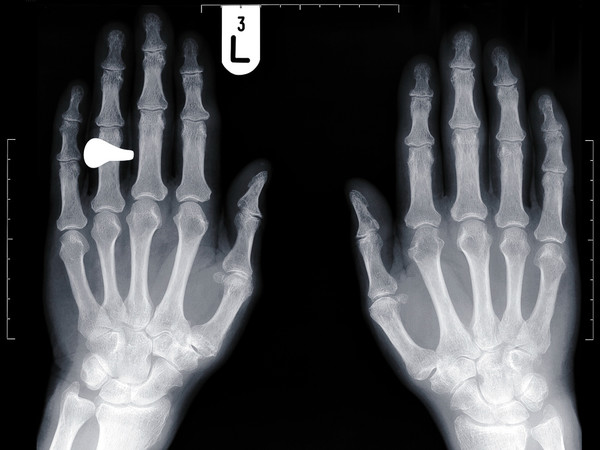

Un reciente estudio de la Universidad de Concordia (EEUU) publicado en Personality and Individual Differences concluía de que la proporción entre la longitud del segundo y el cuarto dedo de la mano es un indicador tanto de los niveles de exposición prenatal a la hormona testosterona como de la predisposición a asumir riesgos eh hombres.

Según un estudio realizado con ratones, la diferencia de tamaño se debe a las hormonas, cuanto mayor es la exposición a la testosterona antes de nacer más despacio crece el dedo índice en relación con la suma del resto de los dedos de la mano, excluido el pulgar. Así, los individuos con el dedo índice más corto son más proclives a arriesgarse tanto en el terreno social como a la hora de ligar, en los deportes o en el ámbito de las finanzas.

Ésta es la razón por la que muchos hombres tienen el dedo anular más largo que el índice, al contrario que las mujeres.